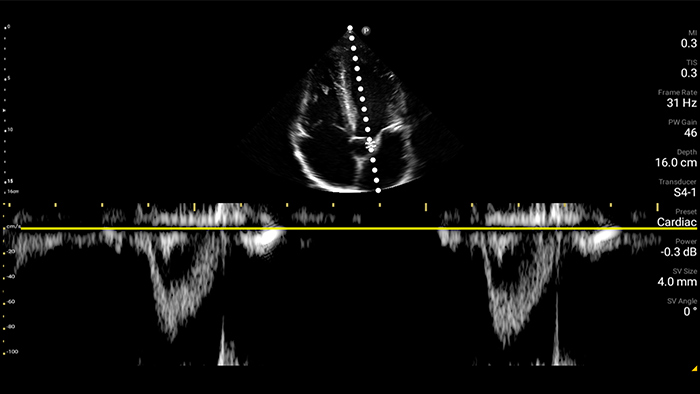

Gebruik Lumify voor luchtweg- en pulmonale beoordeling

De Lumify POCUS-oplossingen kunnen u helpen de endotracheale tube binnen de trachea te detecteren, ondersteuning te bieden bij urgente coniotomieprocedures, en diagnoses te stellen van pleurale effusie en interstitiële alveolaire ziekten.